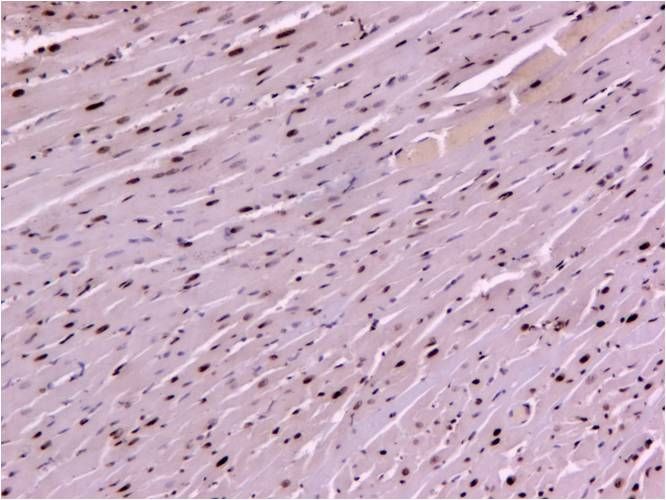

TUNEL-心肌 100倍

TUNEL染色是一種用于檢測細(xì)胞凋亡的靈敏方法。在細(xì)胞凋亡過程中,DNA會發(fā)生斷裂,形成雙鏈或單鏈的缺口。TUNEL染色利用末端脫氧核苷酸轉(zhuǎn)移酶將標(biāo)記的dUTP連接到這些缺口上,從而可以在顯微鏡下觀察到凋亡細(xì)胞的特征性染色。這種染色方法廣泛用于生物學(xué)、病理學(xué)、免疫學(xué)和腫瘤學(xué)的研究,幫助我們理解凋亡在疾病發(fā)展和治療反應(yīng)中的作用。

在實(shí)際研究中,我們經(jīng)常需要將TUNEL染色和DAPI染色結(jié)合起來,以同時觀察細(xì)胞凋亡和細(xì)胞核結(jié)構(gòu)。這種雙重染色方法不僅可以幫助我們確定凋亡細(xì)胞的位置和數(shù)量,還可以進(jìn)一步分析凋亡細(xì)胞與細(xì)胞核結(jié)構(gòu)之間的關(guān)系。例如,在某些疾病中,凋亡細(xì)胞的增多可能與細(xì)胞核結(jié)構(gòu)的異常有關(guān),這種關(guān)系可以通過雙重染色方法得到直觀的展示。